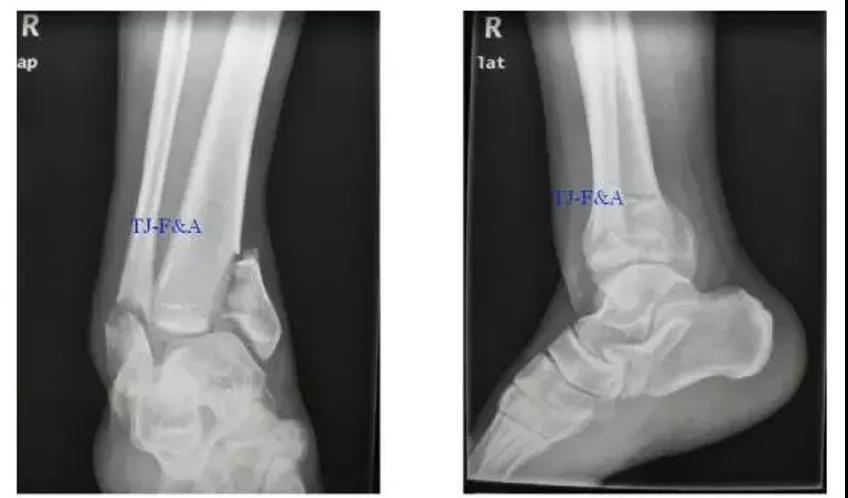

术前

术前DR